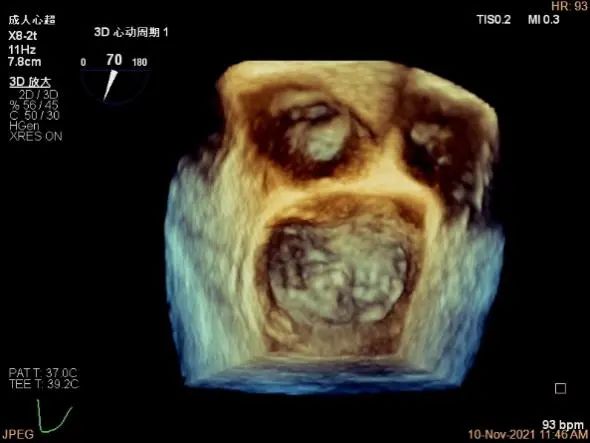

3D MV View:P1区瓣体瘤形成并中央型破裂孔,脱垂从P1到P2区,脱垂宽度13.1mm,破裂孔大小4.1×5.6mm

TEE Bicom view:主要病变区域为P1区,瓣叶中部可见连续性中断